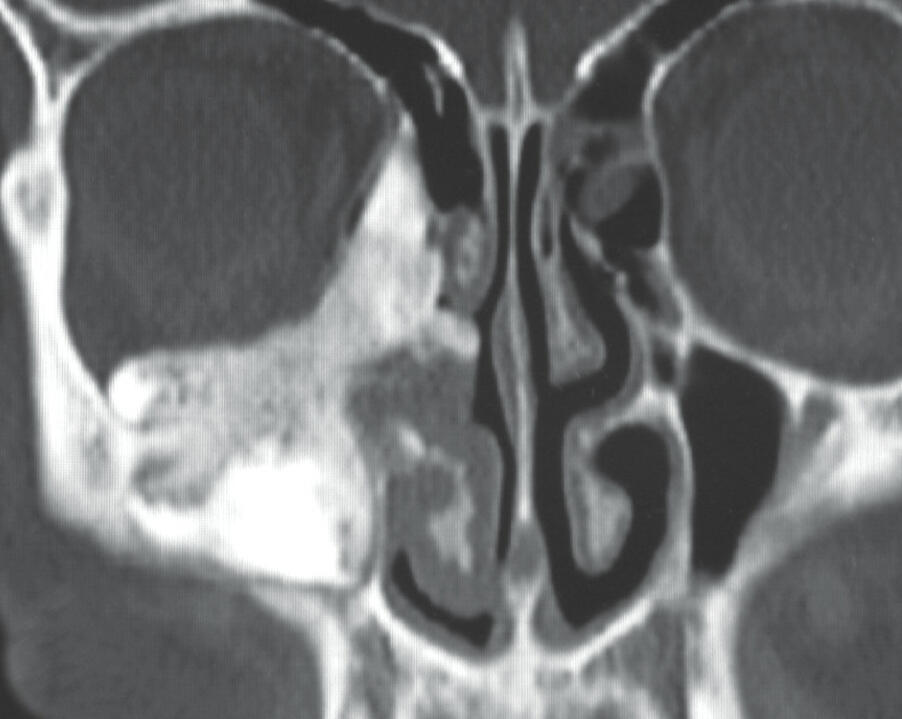

What is the diagnosis?

Median rhomboid glossitis is manifested as a round or rhomboid-shaped patch of smooth

mucosa that lacks both papillae and taste buds and is typically located in the midline just

anterior to the foramen cecum, as in this case. It is thought to arise from an embryologic

defect. If the lesion is symptomatic or atypical in appearance, a biopsy is warranted to rule

out carcinoma. Otherwise, the lesion is benign and requires no treatment.